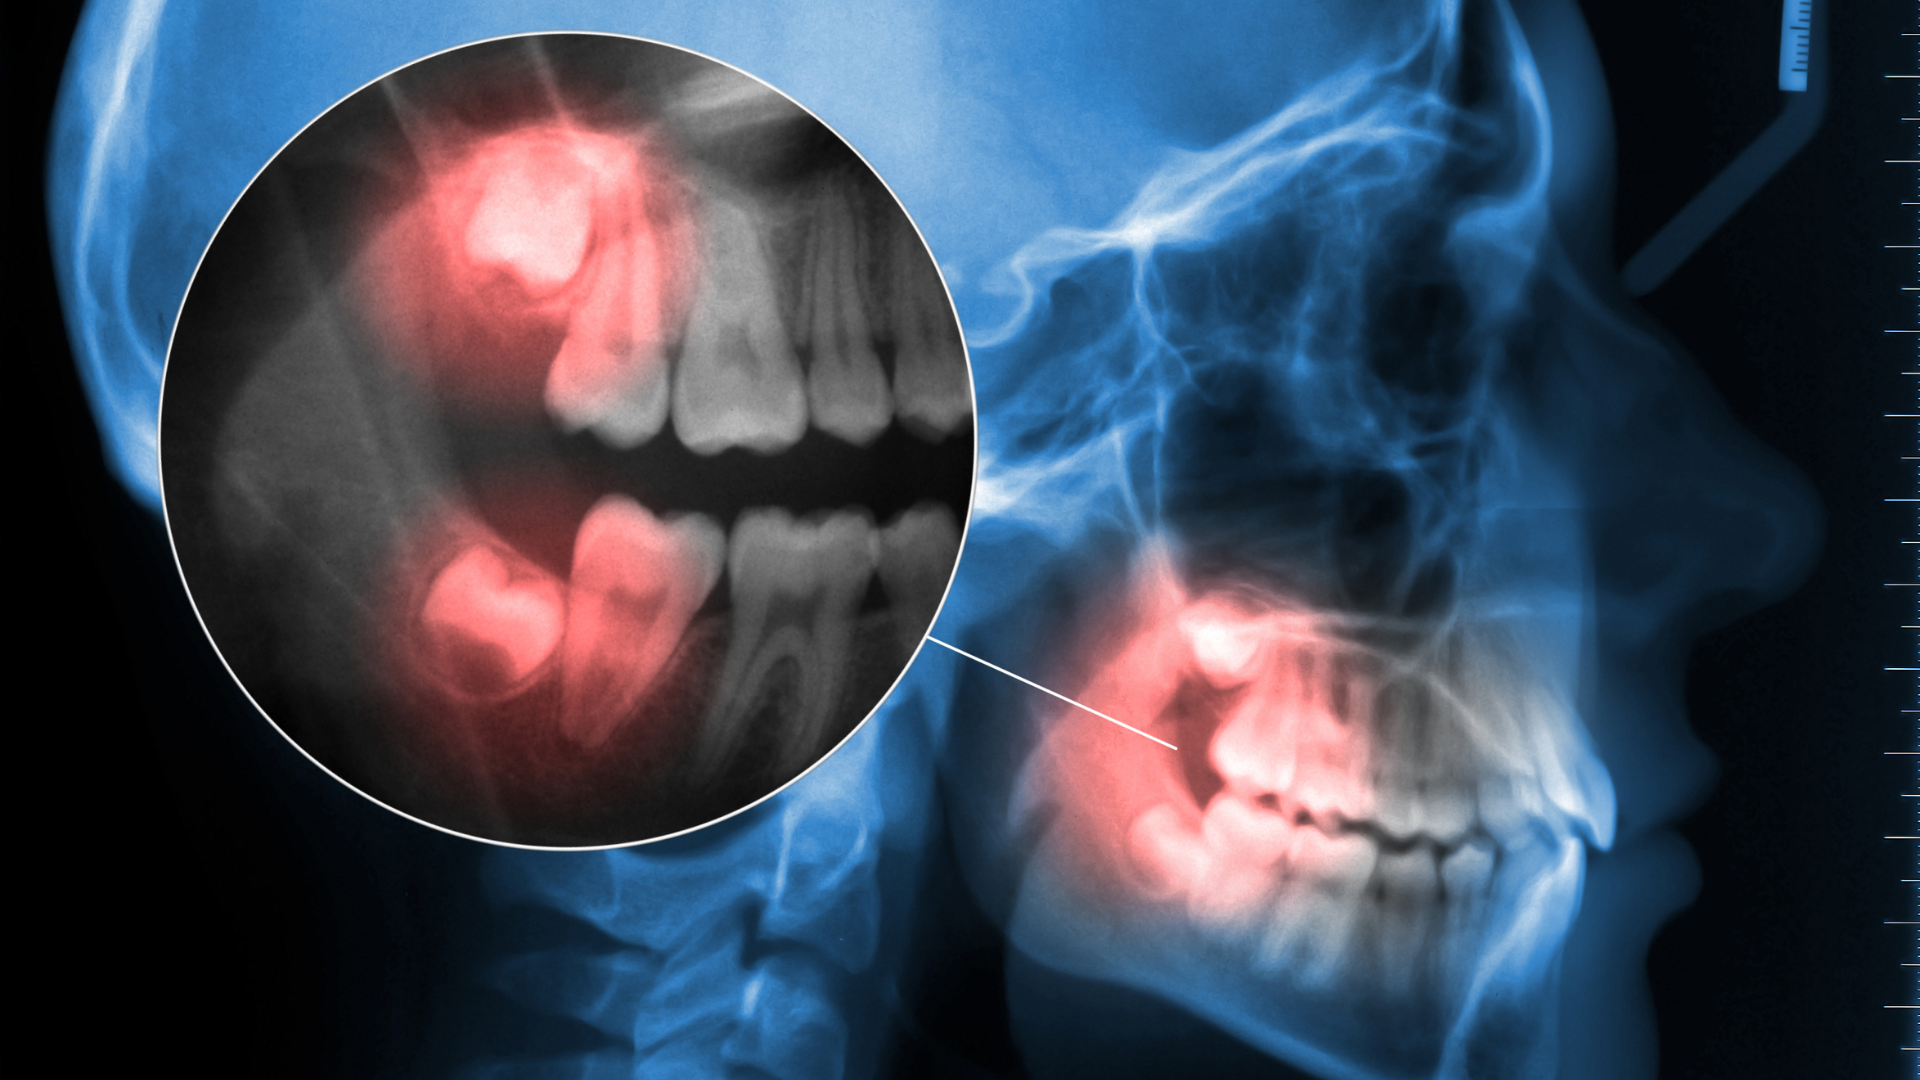

When the jaw breaks near the back corner — known as a mandibular angle fracture — doctors often focus on repairing the bone. But another structure is almost always caught in the damage: the third molar, or wisdom tooth.

Researchers at Wuhan University reviewed 110 cases of patients treated for mandibular angle fractures between 2014 and 2023. Each case involved a wisdom tooth located directly along the fracture line.

They categorized tooth injuries into three new types:

Type I – Complete dislocation: the tooth is forced out of its socket.

Type II – Tooth fracture: the crown or root is broken.

Type III – Stable exposure: the tooth lies along the fracture line but remains intact and unmoved.

Only about 12% of teeth were severely damaged (Types I or II). The vast majority (88%) were Type III — meaning they were affected but structurally sound.